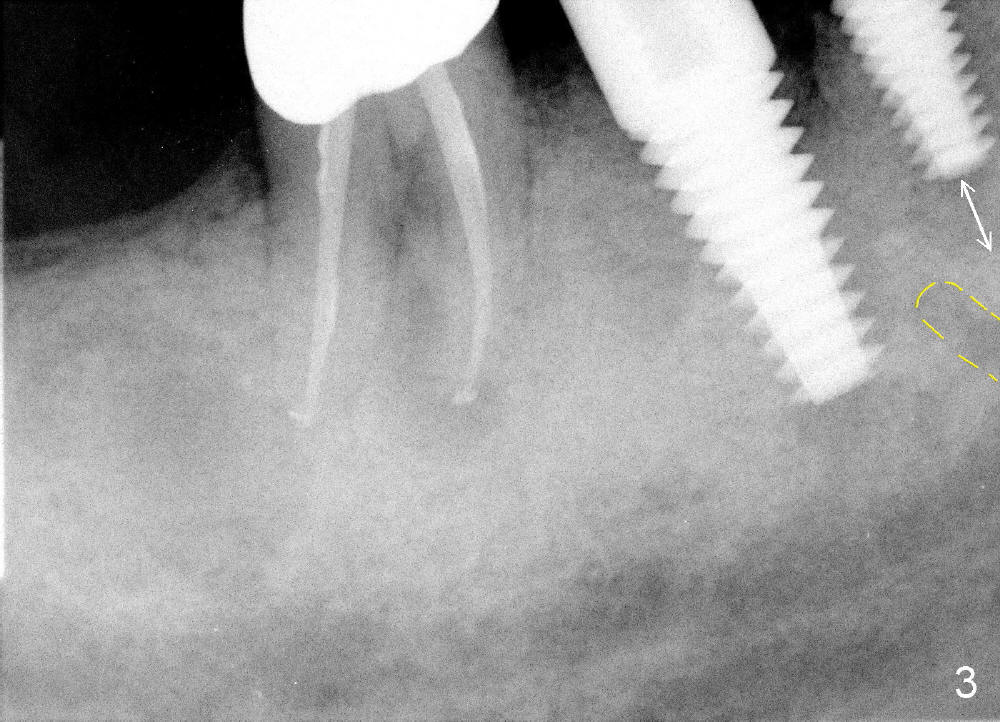

One month after implant placement at the sites of #29,30, the former is found loose (Fig.1,2). It is placed higher than #30. Three weeks later, PA is retaken to confirm that there is space apical to the implant at #29 (Fig.3 double arrows) and that there is distance from the mental loop (yellow dashed line). After infiltration anesthesia, the implant is torqued down initially (compare Fig.4,5) and more (Fig.6,7). To prevent re-loosening, the two implants are splinted (Fig.8).